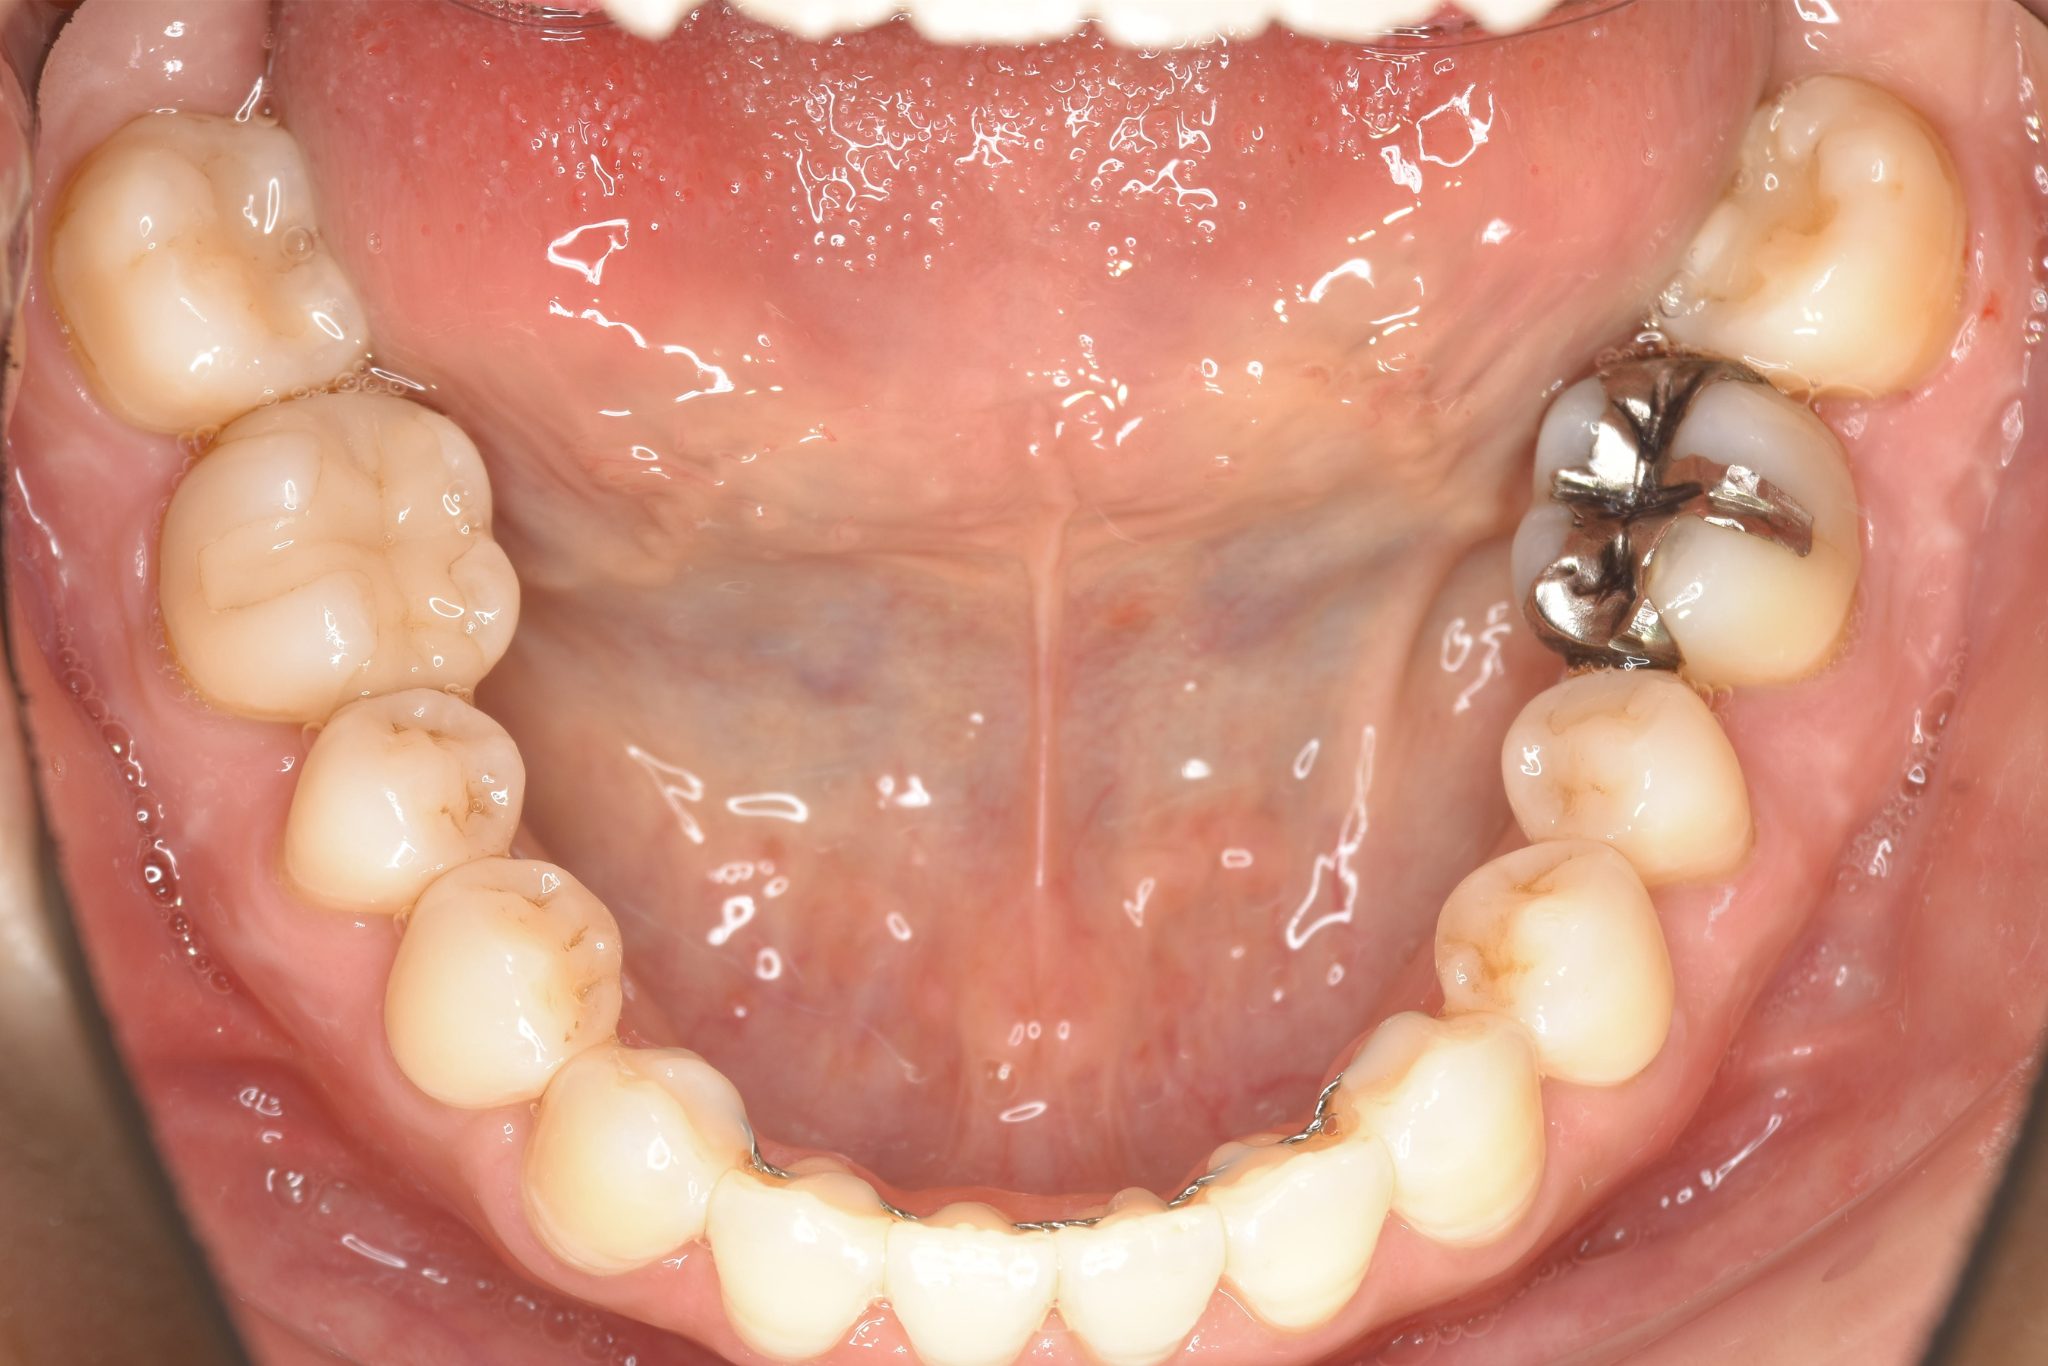

ビフォー

保険での矯正治療|症例_138